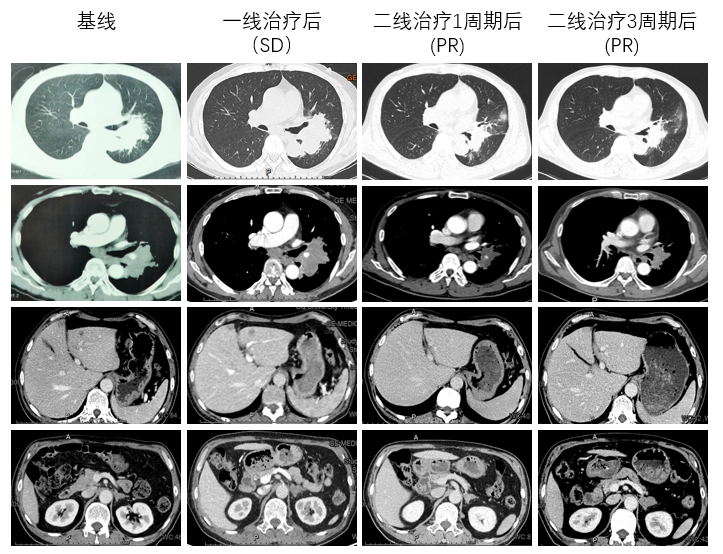

胸部增强CT(2022-05-17):考虑肿瘤性病变伴阻塞性炎症(左肺下叶背段支气管阻塞,肺门处见软组织团块影,呈分叶状,大小约9.8cm×4.6cm,包绕邻近血管);肿块旁多发小结节,子灶?左肺门及纵隔多发转移瘤。

图1.胸部增强CT

复查增强CT(2022-06-29):1.左肺上下叶见不规则形团块影(8.45cm×5.7cm);考虑肿瘤性病变伴阻塞性炎症;肿块旁多发小结节,子灶?左肺门及纵隔多发转移瘤。2.肝脏多发低密度结节影,较大者直径约1.1cm,增强不均匀强化。3.左侧肾上腺结节状增粗、不均匀强化,转移瘤可能。4.左肺下叶点状钙化灶。

第1周期治疗后疗效评估结果:SD。

考虑患者获益不明显,换用二线治疗。

二线治疗第1周期后复查增强CT(2022-07-25):与2022-06-29CT对比:1.左肺上下叶肿瘤性病变(较大截面大小约5.9cm×4.5cm)伴阻塞性炎症,病灶较前缩小;肿块旁多发小结节,考虑转移灶,较前缩小;左肺门及纵隔多发转移瘤,较前缩小。2.右肺上叶及双肺下叶点状影,左肺下叶点状钙化灶。与2022-05-30CT对比:1.左侧肾上腺结节(较大者直径约1.0cm)考虑转移,病灶较前缩小。2.原片所示肝内转移灶本次检查显示欠清晰。

二线治疗第1周期后疗效评估结果:PR。

二线治疗第3周期后复查增强CT(2022-09-25):与2022-07-25CT对比:左肺上下叶肿瘤性病变伴阻塞性炎症(较大截面大小约5.1cm×3.2cm),肿块较前大致相仿,周围炎症较前略有吸收、减少;左肺门及纵隔多发淋巴结转移,部分较前略显缩小。与2022-07-25CT对比:1.左侧肾上腺肿块(最大横截面约3.4×2.1cm),较前增大,考虑肾上腺转移。2.肝右叶小囊肿可能。

二线治疗第3周期后疗效评估结果:肺部及纵隔淋巴结病灶为PR;肝脏病灶为CR;左肾上腺病灶为PD;总体疗效评价为PR。

图5.基线及治疗期间胸腹部CT

该例患者为小细胞癌与鳞癌复合型C-SCLC,初诊伴左肾上腺转移、肝转移,预后差,治疗选择少。该患者一线使用斯鲁利单抗联合依托泊苷+卡铂化疗方案进行治疗1周期后,影像学显示肺部病灶退缩不明显。考虑患者合并鳞癌成分,可能对于EC方案不敏感,因此换用二线治疗方案。经1周期斯鲁利单抗联合白蛋白紫杉醇+卡铂治疗后,患者咳嗽、咳痰症状好转,肿瘤NSE标志物明显下降,影像学提示肺部病灶出现明显退缩,且肝脏转移瘤及左侧肾上腺病灶均较前缩小,疗效达PR。患者使用斯鲁利单抗联合白蛋白紫杉醇+卡铂方案治疗3周期后,影像学检查提示肺部及纵隔淋巴结病灶疗效持续PR,肝脏病灶疗效达CR,仅左肾上腺病灶有PD征象。目前患者正在接受局部放疗,以期进一步提高肿瘤局部控制率。患者治疗期间未出现不可控irAE,安全性好。

该病例为老年吸烟男性,病理类型包含SCLC和sqNSCLC两种不同成分,属于广泛期C-SCLC。根据《2022年CSCO小细胞肺癌诊疗指南》推荐,广泛期C-SCLC的治疗方案可参照SCLC,患者一线治疗给予斯鲁利单抗+EC方案,第一周期治疗后影像学提示肺部病灶退缩不明显,疗效达SD。考虑可能由于C-SCLC中混合的sqNSCLC成分,导致患者对SCLC常规EC方案的敏感性不高,因此进入二线治疗,继续应用斯鲁利单抗免疫治疗,将化疗方案调整为白蛋白紫杉醇+卡铂。调整方案后,患者症状缓解明显,且肿瘤标志物NSE较前明显降低,影像学检查显示全身病灶均出现明显退缩,疗效达PR。患者在斯鲁利单抗联合化疗治疗期间并未发生明显irAE。局部放疗在C-SCLC应用的研究鲜有报道,考虑SCLC对放疗敏感,针对该病例给予了放疗。目前患者病情平稳,无明显不良反应发生。该病例充分证实了斯鲁利单抗在C-SCLC患者中的良好疗效及可耐受的安全性,显示了斯鲁利单抗在肺癌患者中的广阔应用前景。同时,此病例也提示我们,在临床实践中,需结合C-SCLC患者不同病理类型,制订个性化的治疗策略。